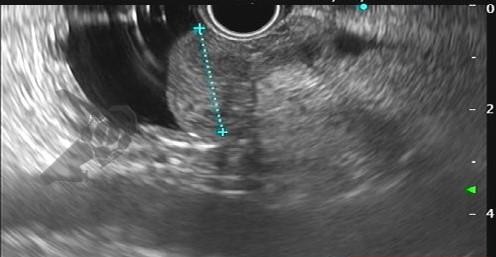

Figuras 1 e 2. Imagem endoscópica em visão direta de lesão protrusa entre pequena curvatura e parede posterior de corpo gástrico proximal, revestida por mucosa com superfície regular, normocorada e íntegra. A imagem ecoendoscópica demonstra lesão com ecogenicidade hipoecoica, ecotextura homogênea, formato ovalado, sem características internas, sem vascularização ao doppler, limites precisos, contornos regulares, medindo aproximadamente 20 x 6 mm e inserida em camada muscular própria. Punções ecoguiadas foram realizadas com agulha FNB, sendo o anatomopatológico e imuno-histoquímica compatíveis com GIST gástrico. Fonte: arquivos do Instituto do Câncer do Estado de São Paulo (ICESP/HCFMUSP)Figuras 1 e 2. Imagem endoscópica em visão direta de lesão protrusa entre pequena curvatura e parede posterior de corpo gástrico proximal, revestida por mucosa com superfície regular, normocorada e íntegra. A imagem ecoendoscópica demonstra lesão com ecogenicidade hipoecoica, ecotextura homogênea, formato ovalado, sem características internas, sem vascularização ao doppler, limites precisos, contornos regulares, medindo aproximadamente 20 x 6 mm e inserida em camada muscular própria. Punções ecoguiadas foram realizadas com agulha FNB, sendo o anatomopatológico e imuno-histoquímica compatíveis com GIST gástrico. Fonte: arquivos do Instituto do Câncer do Estado de São Paulo (ICESP/HCFMUSP)Figuras 3 e 4. Imagem endoscópica em visão direta de abaulamento de parede em segunda porção duodenal distalmente à papila duodenal maior, revestida por mucosa com íntegra, de coloração amarelada e superfície regular. A ecoendoscopia demonstra lesão com ecogenicidade hiperecoica, ecotextura homogênea, formato arredondado, medindo cerca de 10 mm no maior eixo, com limites precisos, contornos regulares, medindo cerca de 10 mm no maior diâmetro e inserida em camada submucosa, sendo os achados endoscópicos e ecoendoscópicos compatíveis com lipoma.Figuras 3 e 4. Imagem endoscópica em visão direta de abaulamento de parede em segunda porção duodenal distalmente à papila duodenal maior, revestida por mucosa com íntegra, de coloração amarelada e superfície regular. A ecoendoscopia demonstra lesão com ecogenicidade hiperecoica, ecotextura homogênea, formato arredondado, medindo cerca de 10 mm no maior eixo, com limites precisos, contornos regulares, medindo cerca de 10 mm no maior diâmetro e inserida em camada submucosa, sendo os achados endoscópicos e ecoendoscópicos compatíveis com lipoma.Fig. 5. Imagem endoscópica em visão direta de lesão protrusa em parede anterior de antro gástrico proximal, revestida por mucosa normocorada, com superfície regular, sendo sugestiva de lesão subepitelial.Fig. 6. A ecoendoscopia evidencia lesão com ecogenicidade hipoecoica, ecotextura predominantemente homogênea, formato arredondado, limites precisos, bordos regulares, medindo aproximadamente 13,4 x 12 mm, sem focos hiperecoicos ou calcificações no interior e inserida na camada muscular própria. Punções ecoguiadas foram realizadas com agulha FNB, sendo anatomopatológico e imuno-histoquímica confirmando schwanomma gástrico.Fig. 7 e 8. Imagem de esofagogastroduodenoscopia demonstra lesão protrusa em papila duodenal maior revestida por mucosa enantemática e com superfície com três erosões recobertas por fibrina.Fig. 7 e 8. Imagem de esofagogastroduodenoscopia demonstra lesão protrusa em papila duodenal maior revestida por mucosa enantemática e com superfície com três erosões recobertas por fibrina.Fig. 9 e 10. Imagem à ecoendoscopia demonstra lesão com formato ovalado, ecogenicidade hipoecoica, ecotextura heterogênea, com contornos regulares, sem adenopatia adjacente, sem vascularização ao doppler, sem características internas, medindo cerca de 20 x 11 x 24 mm, inserida na camada submucosa, não havendo acometimento da muscular própria. Foram realizadas punções ecoguiadas com agulha FNA 22 gauge, sendo o anatomopatológico e imunohistoquímica compatíveis com tumor neuroendócrino de papila duodenal bem diferenciado grau 1.Fig. 9 e 10. Imagem à ecoendoscopia demonstra lesão com formato ovalado, ecogenicidade hipoecoica, ecotextura heterogênea, com contornos regulares, sem adenopatia adjacente, sem vascularização ao doppler, sem características internas, medindo cerca de 20 x 11 x 24 mm, inserida na camada submucosa, não havendo acometimento da muscular própria. Foram realizadas punções ecoguiadas com agulha FNA 22 gauge, sendo o anatomopatológico e imunohistoquímica compatíveis com tumor neuroendócrino de papila duodenal bem diferenciado grau 1.Fig. 11 e 12. Esofagogastroduodenoscopia demonstra abaulamento de parede anterior de corpo gástrico proximal, com mucosa normocorada, superfície regular com depressão central, sendo compatível com lesão subepitelialFig. 11 e 12. Esofagogastroduodenoscopia demonstra abaulamento de parede anterior de corpo gástrico proximal, com mucosa normocorada, superfície regular com depressão central, sendo compatível com lesão subepitelialFig. 13 e 14. Ecoendoscopia demonstrou formação com ecogenicidade hipoecoica, ecotextura homogênea, formato ovalado, limites bem definidos, contornos regulares, medindo aproximadamente 13 mm e inserida na camada submucosa. Lesão foi submetida a ressecção endoscópica transmural com dispositivo FTRD. A histopatologia e imunohistoquímica confirmaram TNE gástrico bem diferenciado grau 2.Fig. 13 e 14. Ecoendoscopia demonstrou formação com ecogenicidade hipoecoica, ecotextura homogênea, formato ovalado, limites bem definidos, contornos regulares, medindo aproximadamente 13 mm e inserida na camada submucosa. Lesão foi submetida a ressecção endoscópica transmural com dispositivo FTRD. A histopatologia e imunohistoquímica confirmaram TNE gástrico bem diferenciado grau 2.